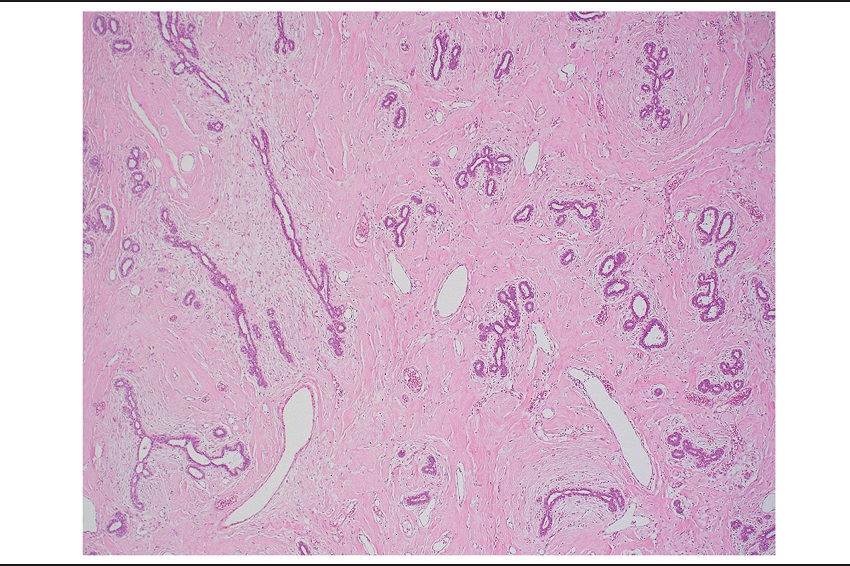

Upon examination by light microscopy, the tumor was composed of a densely collagenous stroma containing numerous anastomosing slit-like spaces, which appeared almost empty and intermixed benign breast ducts and lobules (Figure 1). Stromal spindle cells bordering these spaces resembled endothelial cells. Their nuclei were attenuated, lacked atypia and had no mitotic activity (Figure 2). The spaces were empty. These findings were diffusely and homogeneously seen throughout the whole tumor, which did not contain adipose tissue. The epithelial component comprised breast ducts and lobules, which in some areas had a normal appearance and in others, fibroadenomatoid changes with compressed ducts. The stroma was abundant and predominated over the epithelial component. Focal usual ductal hyperplasia and ductal dilatation were present. Stromal myxoid change were seen (Figure 3). Some areas had abundant edematous loose stroma with few intervening epithelial elements (Figure 4). The presence of these two latter features, along with a predominance of stroma led to an initial diagnosis of benign phyllodes tumor by the general surgical pathologist.

Microscopically, PASH is composed of benign breast parenchyma with an admixture of stroma and epithelial structures. The lesion is defined by the presence of complex often anastomosing spaces involving both intralobular and interlobular stroma, which is typically expanded and densely collagenous. Myofibroblasts line the spaces in a discontinuous fashion, resembling endothelial cells. These cells often have elongated bland nuclei with no atypia or mitotic activity. The stromal component is often increased with wider separation of ducts and lobular units when compared to the usual arrangement. Collagenization of intralobular stroma with duct attenuation commonly leads to a fibroadenomatoid appearance, which was seen in this case, and likely represented the feature that, along with the large tumor dimension, abundance of stroma and myxoid changes, led to an erroneous initial interpretation of benign phyllodes tumor. Usual ductal hyperplasia and ductal dilatation are common in PASH, and both findings were present in this case.

Benign phyllodes tumor has close histologic resemblance to fibroadenoma and is always an important consideration in large tumors. Both may show myxoid change in the stroma that is unusual in PASH, but that was seen in this case, contributing to the initial misinterpretation of benign phyllodes tumor. However, this case did not have two key features for the diagnosis of benign phyllodes tumor, namely leaf-like architecture and hypercellular stroma.